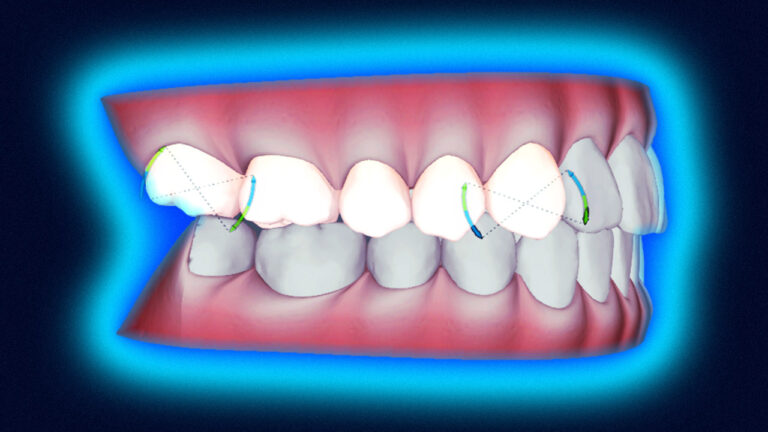

Czym jest elektrokoagulacja? Elektrokoagulacja to zabieg polegający na kontrolowanym wykorzystaniu prądu elektrycznego w celu zamknięcia naczyń krwionośnych oraz usunięcia zmienionych tkanek. W stomatologii metoda ta znajduje zastosowanie przede wszystkim w chirurgii i periodontologii. Stomatolog w nowoczesnej klinika stomatologiczna Kraków wykorzystuje…